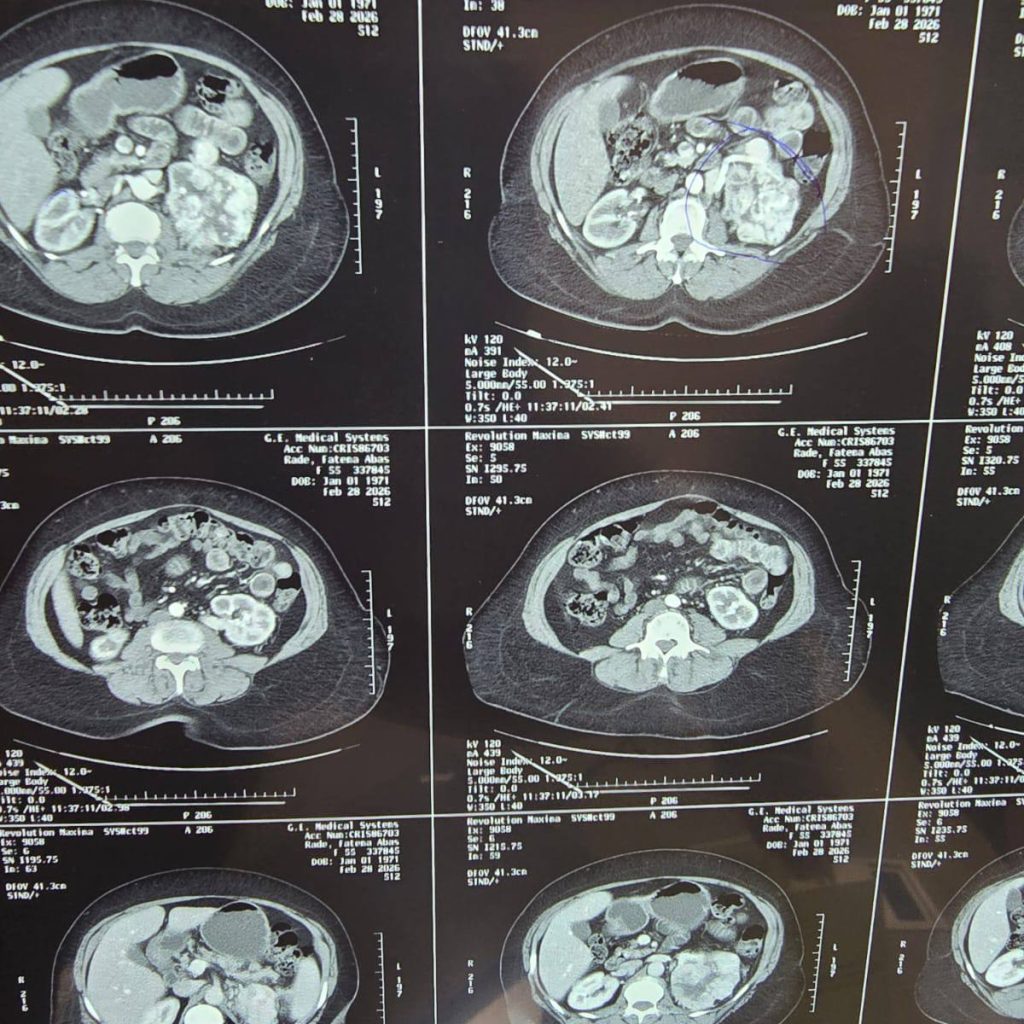

وقدّمت المريضة إلى المستشفى بأعراض ألم حاد ومفاجئ في الخاصرة، ما استدعى إجراء تقييم سريري شامل مدعوم بفحوصات مختبرية وتصوير مقطعي محوسب معزز بالصبغة (contrast-enhanced CT).

وأظهرت النتائج وجود كتلة ورمية كبيرة في الكلية اليسرى، مع مؤشرات واضحة تستوجب التدخل الجراحي عبر الاستئصال الجذري للكلية المصابة.